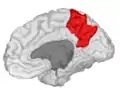

Precuneus

The precuneus is the portion of the superior parietal lobule on the medial surface of each brain hemisphere. It is located in front of the cuneus (the upper portion of the occipital lobe). The precuneus is bounded in front by the marginal branch of the cingulate sulcus, at the rear by the parietooccipital sulcus, and underneath by the subparietal sulcus. It is involved with episodic memory, visuospatial processing, reflections upon self, and aspects of consciousness.

Precuneus of left cerebral hemisphere (shown in red).

Medial surface of left cerebral hemisphere. (Precuneus visible at top left.)